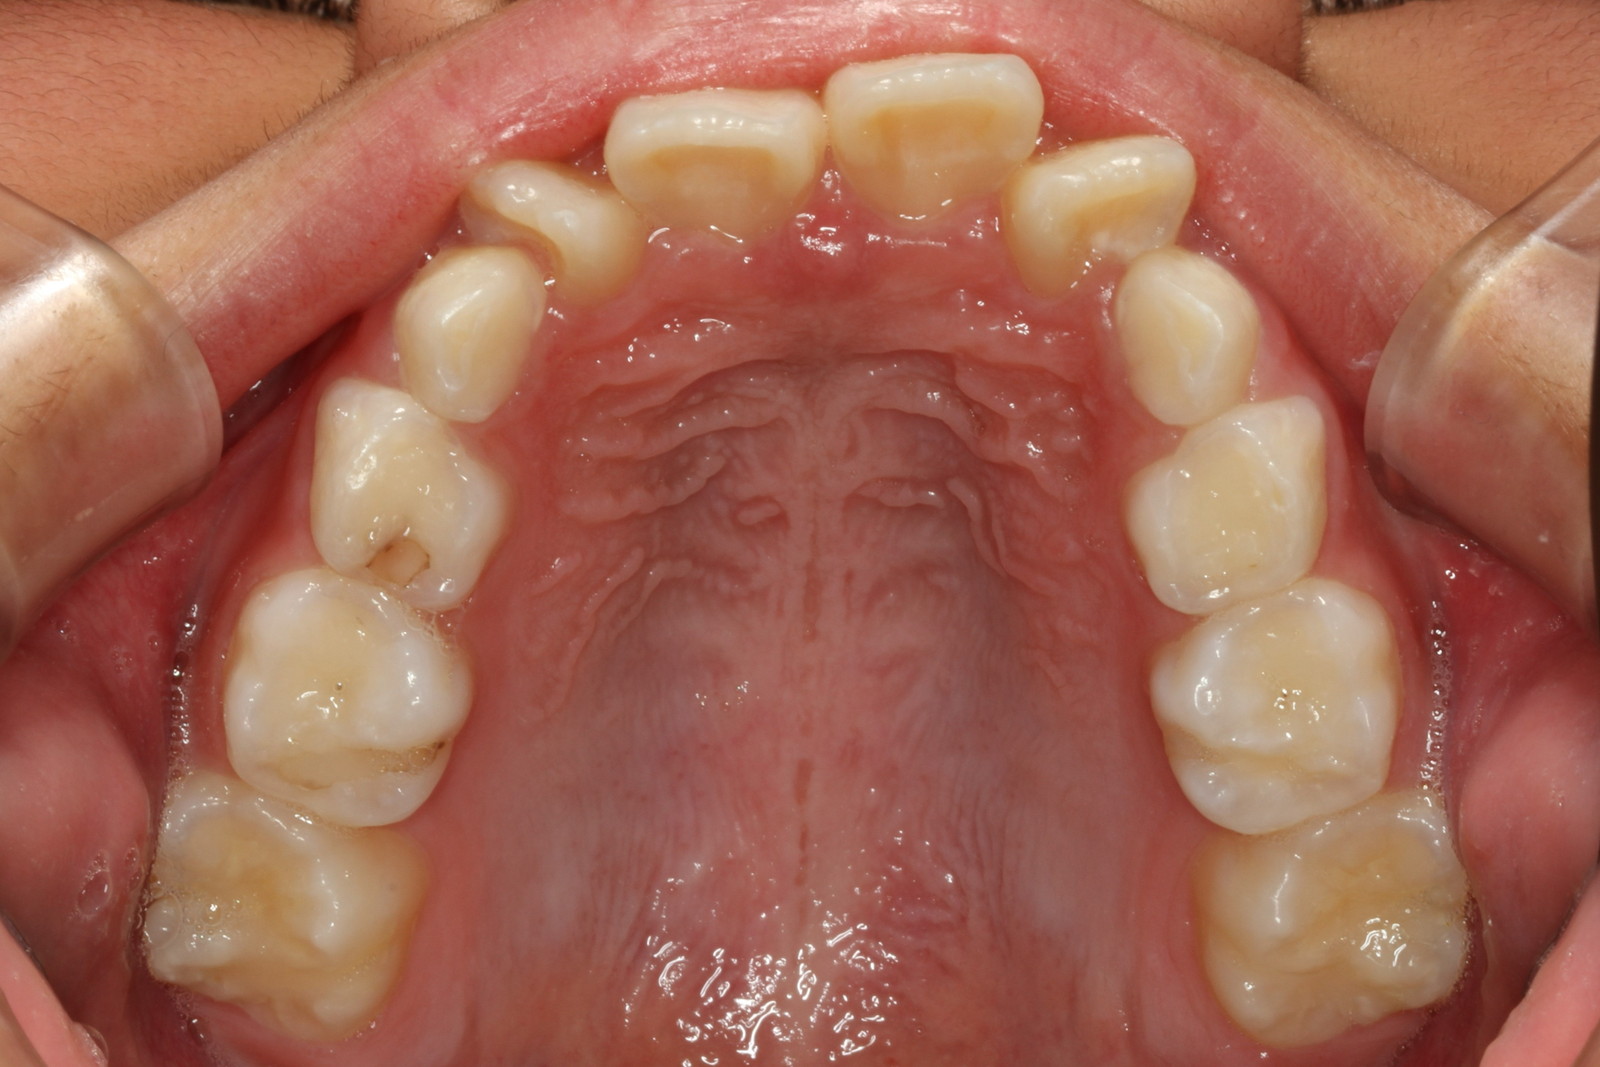

問診を行い、お口の悩みや希望を確認します。レントゲン撮影や口腔内写真の撮影など、必要に応じた精密検査を行います。